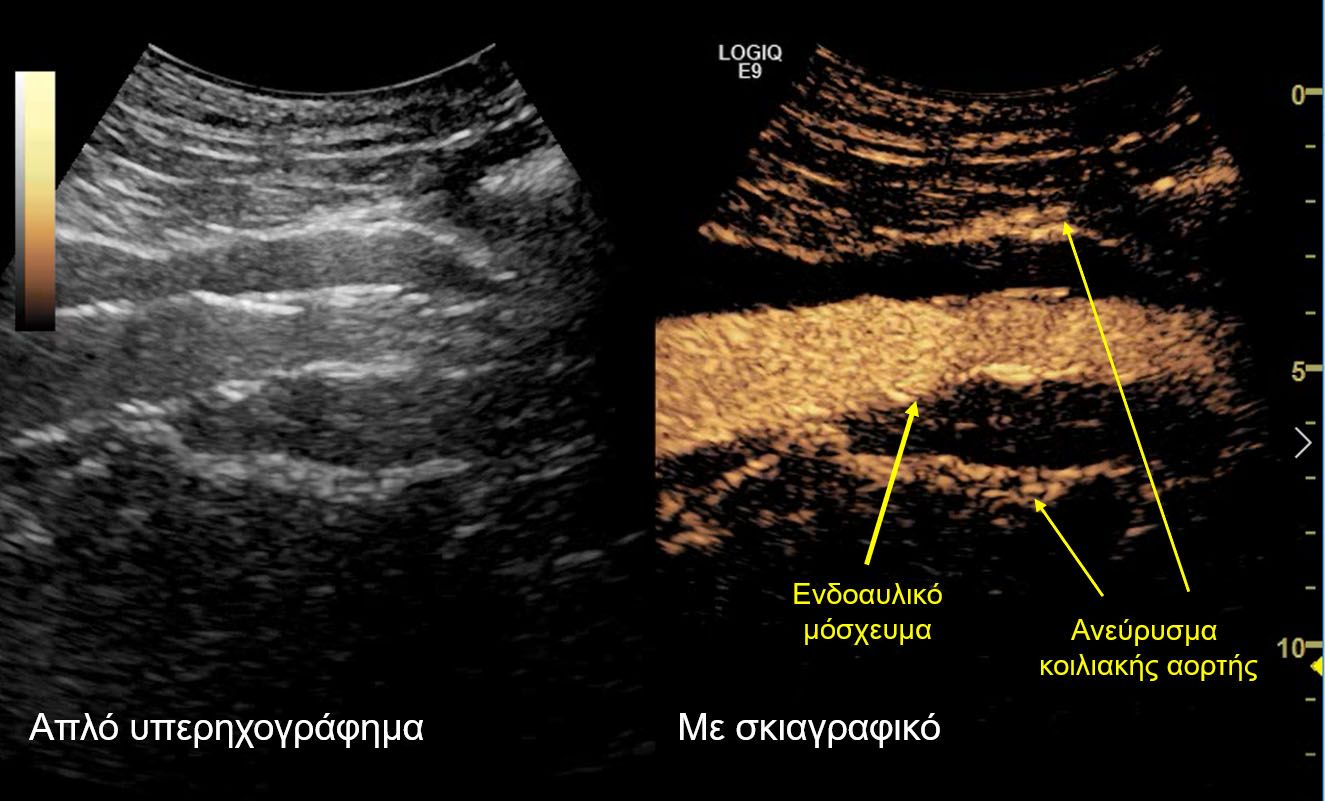

Σε αυτό το πλαίσιο εντάσσεται και ο μετεγχειρητικός υπερηχογραφικός έλεγχος που διεξήχθη στο Τμήμα Υπερήχων από τη Δρ. Κωνσταντίνα Κυριακοπούλου, MD, PhD, Διευθύντρια Τμήματος Υπερήχων, Ιατρικό Κέντρο Αθηνών και τον Ταξιάρχη Καράμπελα, MD, Ακτινολόγο, Αναπληρωτή Διευθυντή Τμήματος Υπερήχων, Ιατρικό Κέντρο Αθηνών. Το κέντρο αυτό ανήκει στα ελάχιστα ευρωπαϊκά κέντρα, τα οποία ελέγχουν τη βατότητα των σπλαγχνικών αγγείων και την επιτυχή ενδοαγγειακή αποκατάσταση των ανευρύσματων υπερηχογραφικά, με τη χρήση ειδικού σκιαγραφικού (SonoVue) που μεταβολίζεται αποκλειστικά στο ήπαρ. Αυτό αποτελεί ιδιαίτερο πλεονέκτημα σε ασθενείς με επηρεασμένη νεφρική λειτουργία.